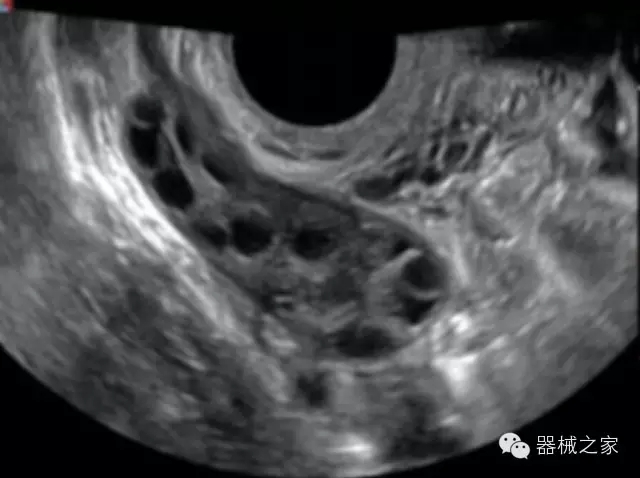

·完整的3D/4D臨床應用,STIC, MCUT 和Auto NT等滿足產(chǎn)科所有應用;

·更高的HQ羊膜腔鏡成像技術(shù)精細觀察每一個暗區(qū)細節(jié);

·高效3D/4D成像技術(shù):高速的4D幀頻,豐富的3D成像模式,智能斷層切片功能;

·獨有的大角度及實時溫控技術(shù),能同一切面顯示宮頸及宮體,有效減低了患者的痛苦,及保護粘膜保證了醫(yī)療安全;